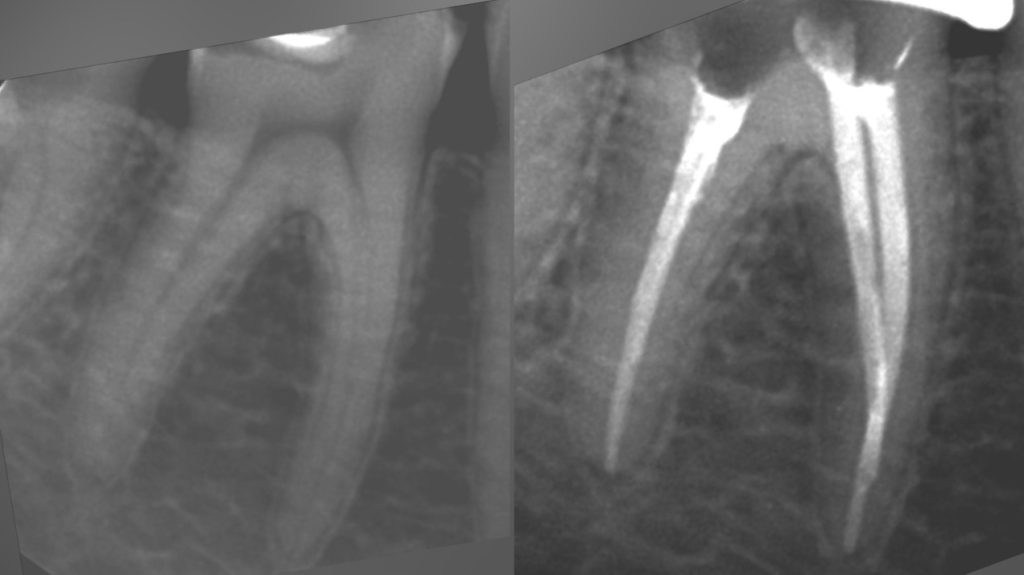

• Эндодонтическое лечение корневых каналов с использованием стоматологического микроскопа

2022 год – «Первичная эндодонтия с использованием современных клинических протоколов» Андрей Кольба

2023 год – «Первичная эндодонтия» Виталий Весна

2025 год – «Современные протоколы лечения эндодонтических пациентов» Dental Education Clinic,курс Елены

Драган